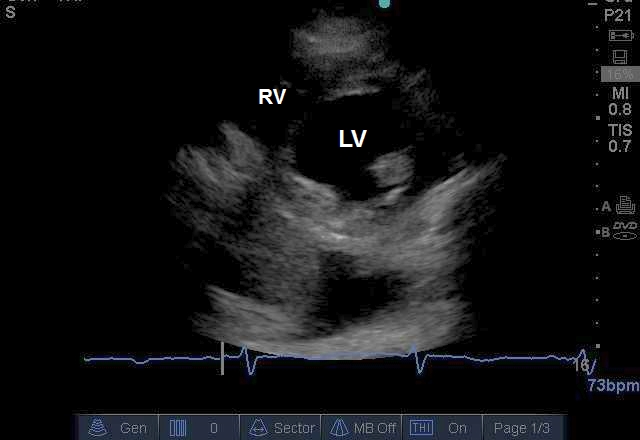

Case 7-2. Parasternal Short-axis View at the Midventricular Level

Video 7-2A. Left ventricular (LV) function is normal. The right ventricle is normal in size and there is no septal dyskinesia.